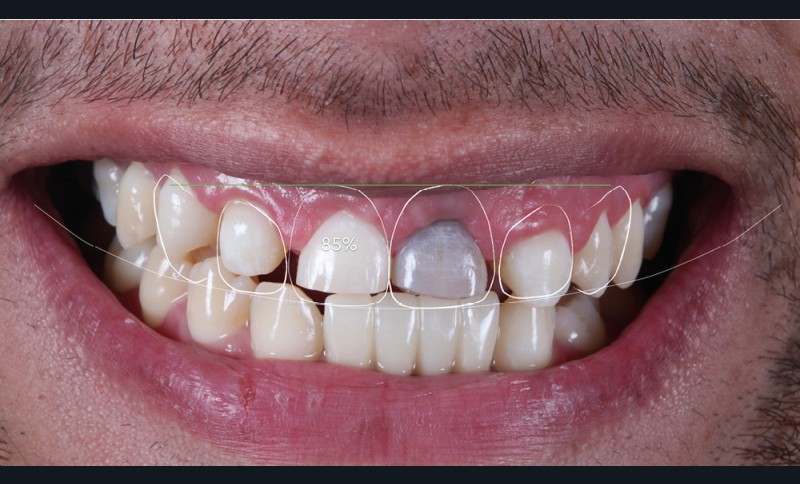

Acte 1 : consultation (fig. 1)

Le patient présente des agénésies génétiques multiples : sur le secteur maxillaire antérieur, il lui manque les deux latérales 12 et 22 ainsi que la canine droite 13 (fig. 1).

Celle du visage d’abord, qui met en évidence un décalage des axes importants : la ligne horizontale maxillaire et la ligne bipupillaire sont loin d’être parallèles. La ligne interincisive part en diagonale, induisant un effet largement inesthétique [2].

L’analyse du sourire du patient révèle une difficulté supplémentaire : haute, la ligne du sourire expose les collets et la gencive, ce qui rend le cas complexe.

Au niveau endobuccal sont observés un défaut des proportions dentaires et une dyschromie importante sur 21.